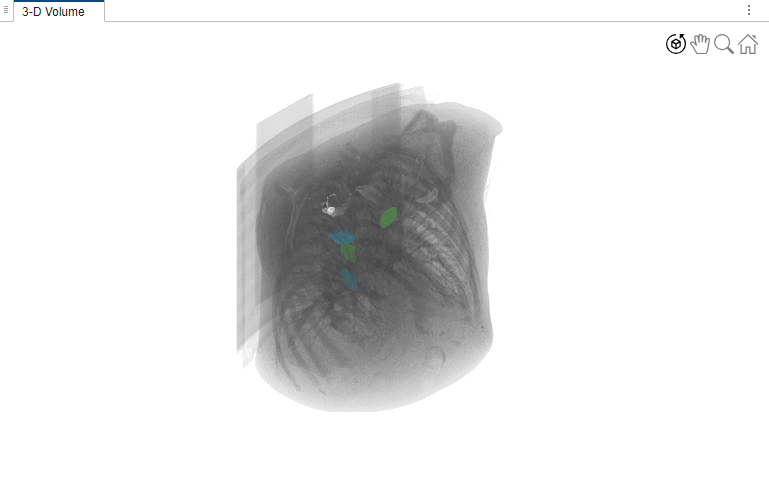

Visualize Labels in 3-D

Visualize the labels in different cross-sections of the volume in the 3-D volume rendering pane.